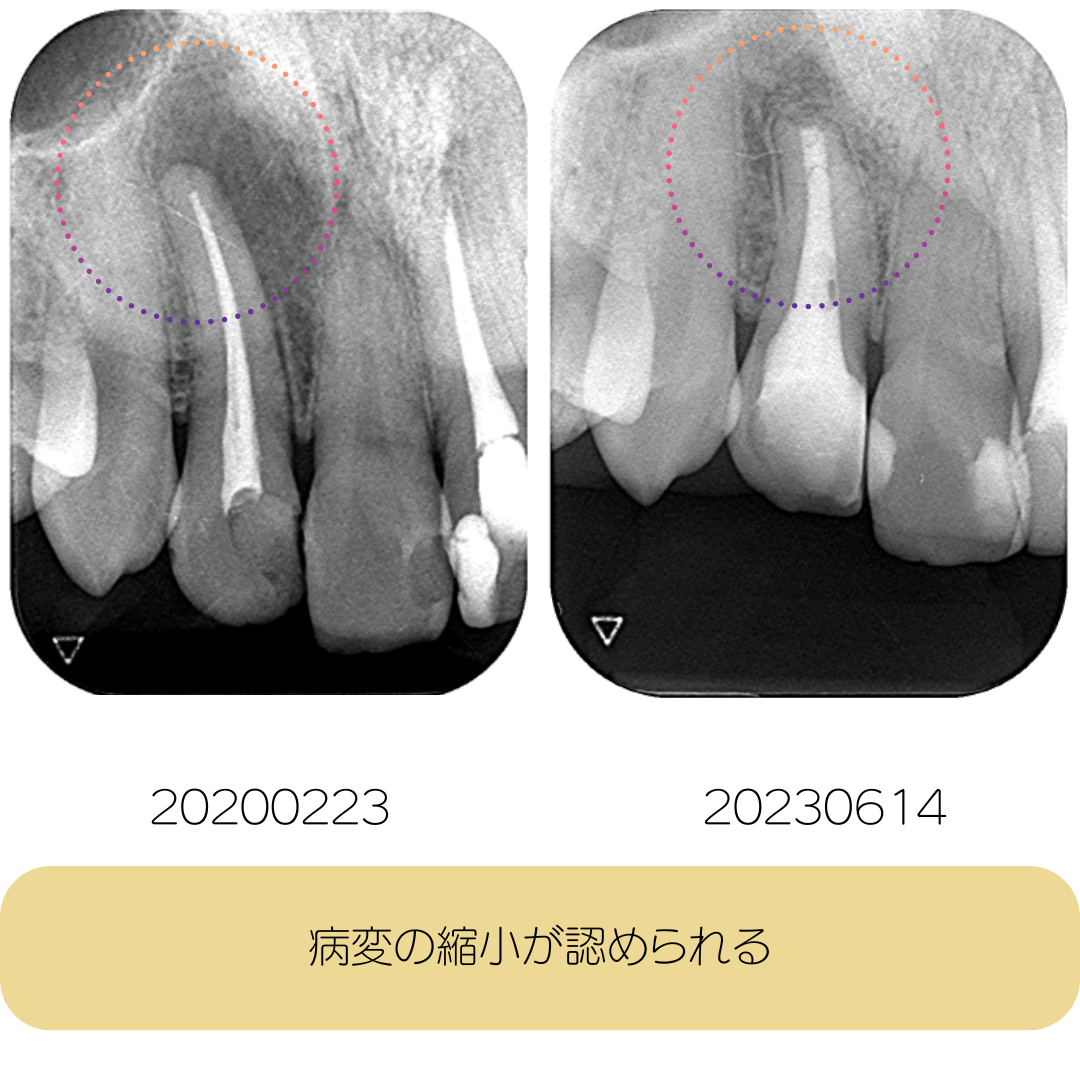

術前術後の写真

まずは結果からご覧ください。歯根にある大きな病変が小さくなっていることがわかります。

術前から術後3年までの経過(時系列)

治癒の経過がよく分かると思います。術後3年経過していますが、再発することなく安定しています。